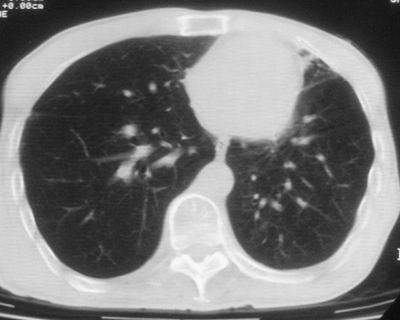

标题: CT11864:男,47岁,反复咳嗽、咯痰、咯血3年,请分析. [打印本页]

标题: CT11864:男,47岁,反复咳嗽、咯痰、咯血3年,请分析.

患者,男,47岁,反复咳嗽、咯痰、咯血3年,再发5天。痰培养未找到真菌、抗酸杆菌、癌细胞。

左肺上叶体积明显缩小,其内见多发透光区,纵隔向左侧移位,左肺下叶多发班片状病灶,边界模糊,1左肺上叶先天肺发育不全,2左肺下叶肺炎,

左肺上叶结核伴肺纤维化,纵隔移位,左肺下叶感染性病变,建议抗炎抗结核后复查,双肺气肿.

1.左肺上叶慢纤空2.左肺下叶炎症

考虑:左肺慢纤伴霉菌球形成、双肺全小叶型肺气肿。

1)考虑为:左肺上叶肺结核(空洞形成),伴左下肺感染;不排除霉菌感染可能。2)肺气肿。

左肺上叶结核伴肺纤维化空洞形成并左肺下叶感染,纵隔牵拉移位,建议作进一步检查排除左侧肺霉菌感染可能。